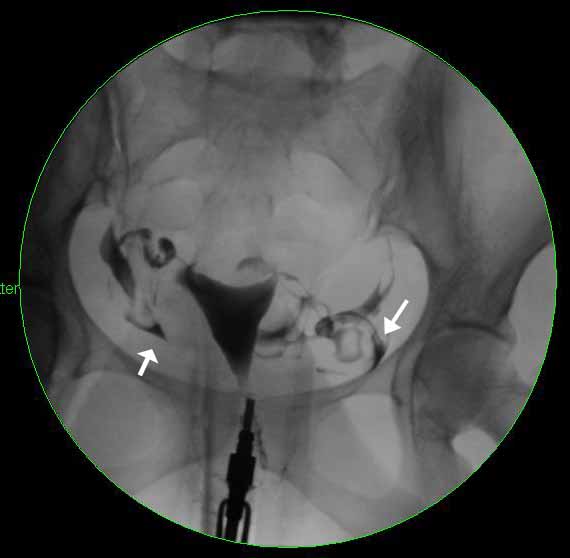

Image 1

This image shows an early radiograph from a normal HSG. The white arrowhead is pointing towards the uterus, which is filled with contrast (the dark, radiopaque material), and is normal in shape. The white arrows are pointing towards the right and left fallopian tubes which are both beginning to fill with contrast.